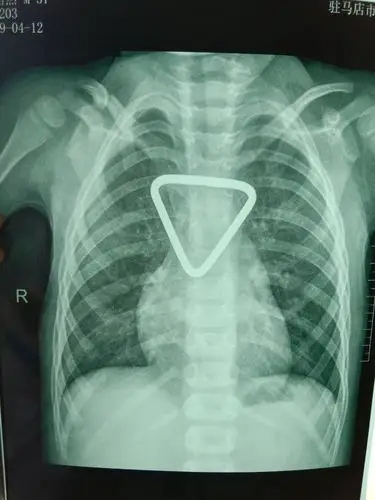

术前锁骨正位片提示锁骨中段骨折,移位明显.

生命体征平稳,患者左锁骨中段粉碎性骨折,骨折缩短移位,复位骨折端